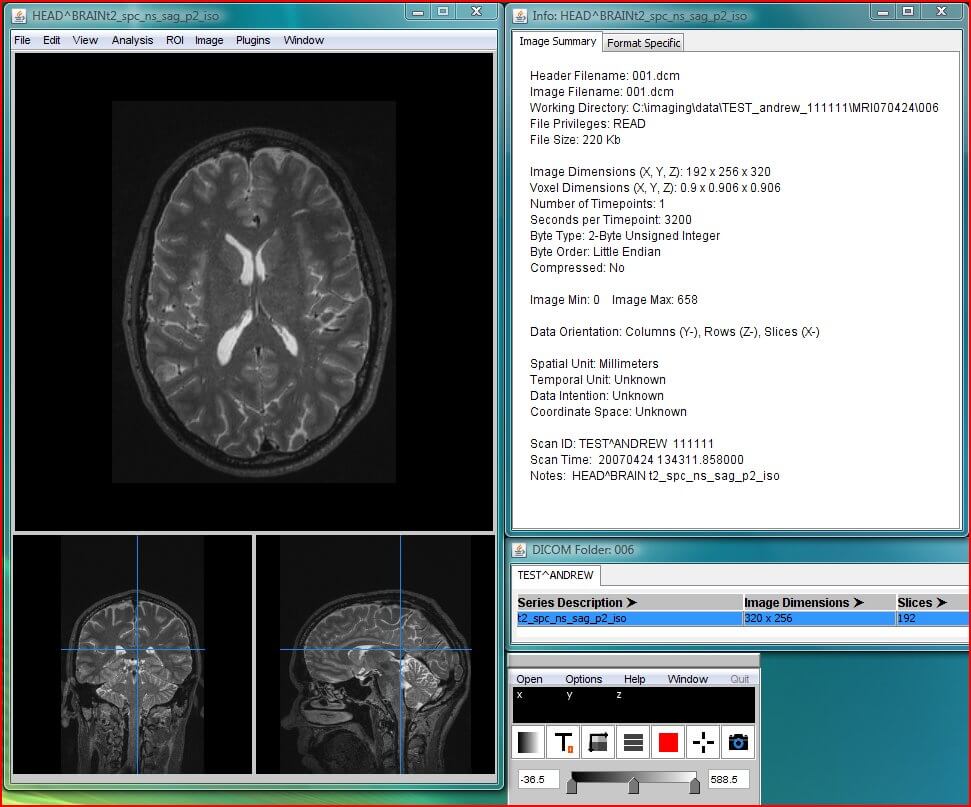

The RadiAnt DICOM image viewer is a simple, fast platform that is compatible with Windows. It offers multiple features, including MPR, MIP, and image fusion. Images can be exported to JPEG, PNG, and other image formats. They can also be copy-pasted directly to presentations and word documents.

The application is just a viewer and does not offer storage space. Their website has a disclaimer explicitly stating that they do not have any certifications, and as such, the product is not intended for diagnostic use. However, it is handy for students and residents for studying medical images and research purposes.